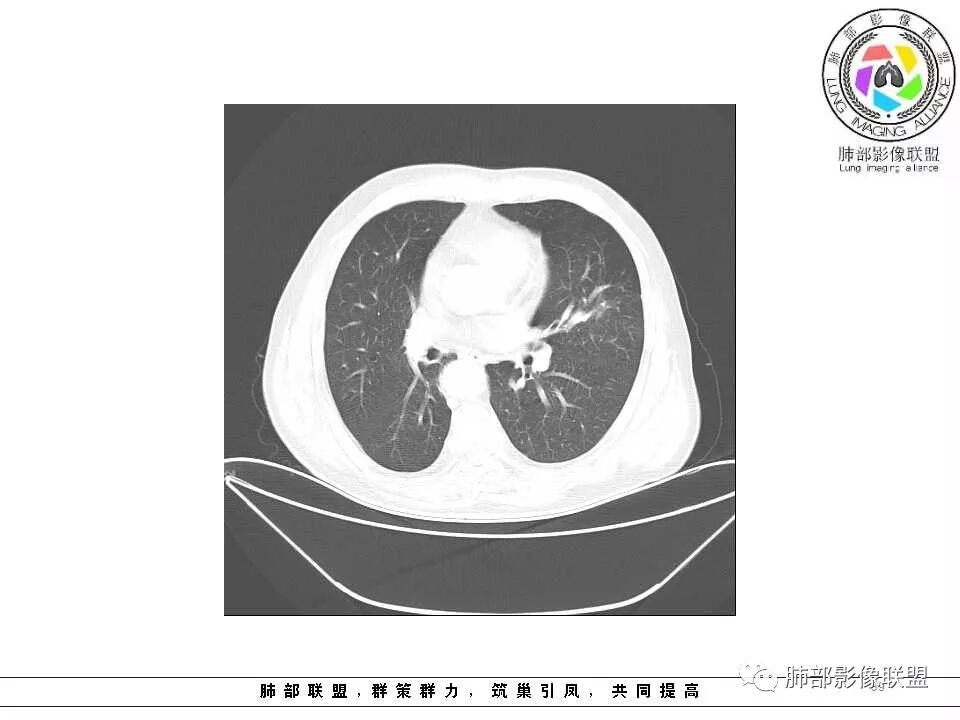

老年男性,左肺舌段见多个小结节灶及斑片状高密度灶、磨玻璃影,结节灶边界清晰,光滑,无明显分叶,密度均匀,周围病灶密度不均,一年内生长,考虑恶性肿瘤并阻塞性肺炎出血,小细胞可能大。

老年男性,肺气肿背景,左肺上叶舌段病灶明显增大,变异膨隆,远端阻塞肺炎,考虑鳞癌。

老年男性,肺气肿背景,左肺上叶舌段结节明显增大,边缘膨隆,有磨玻璃结节,与血管联系紧密,周围可见条片影,首先考虑恶性肿瘤,鳞癌伴阻塞性炎症,鉴别炎性

肺气肿背景,2016年左肺上叶上舌段见微结节,2017年5月左肺结节增大,密度均匀,边缘光滑锐利,与邻近血管关系密切,血管贴壁走行,外侧见尖状突起,下舌段片状影,沿着支气管走行,内有粘液栓,考虑鳞癌,鉴别小细胞肺癌。

肺气肿背景,左肺上舌叶结节一年复查明显增大,边缘光滑。下舌叶片状影,界限模糊。考虑上舌叶小细胞癌并下舌叶感染。鉴别鳞癌

肺气肿背景,2016年左肺上叶上舌段见微结节,一年后左肺结节增大,密度均匀,边缘光滑、膨隆,似见小分叶,下舌段片状影,沿着支气管走行,内,老年患者,咯血1月。考虑恶性病变并阻塞性肺炎,鳞癌?注意鉴别结核。

前次片2016年4月20相应位置就有小点状病灶,2017-5-15呈结节影改变,边界膨隆,远端阻塞炎性改变,考虑肺癌,鉴别炎性结节!